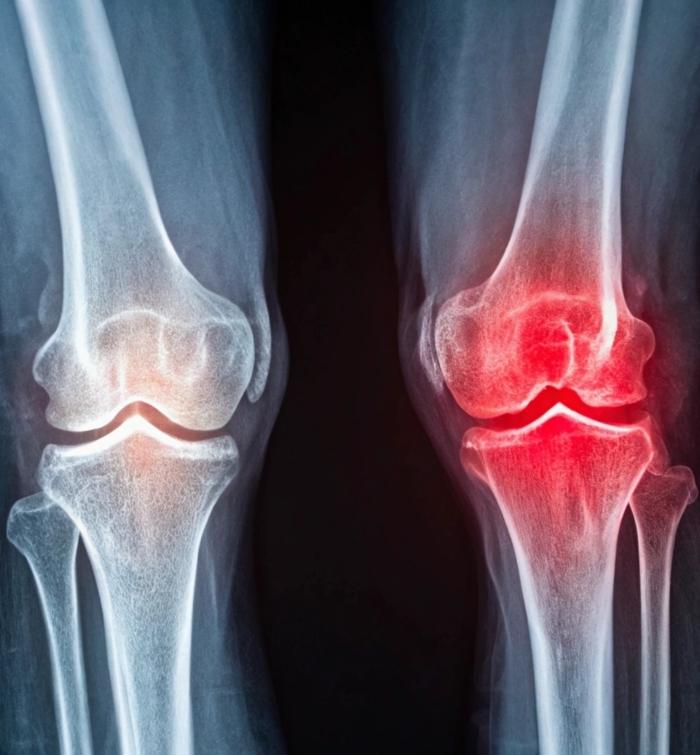

Dealing with knee pain and stiffness can be very uncomfortable, especially after you have already been through a total knee replacement surgery. To address knee issues, you need the help of a professional medical team. The experienced Texas knee replacement surgeons at Eminent Medical Center provide professional care for those experiencing a wide range of knee issues. Whether your pain stems from implant loosening, joint instability, or damaged tissue, our team can help.

A knee replacement surgery, also called knee arthroplasty, is the initial surgery on your knee to replace damaged parts of the joint with metal, ceramic, or plastic components. Many who have a knee replacement enjoy years of pain relief and improved movement. In some cases, the artificial knee joint can stop working correctly over time. If this happens, you may need a second surgery to repair or replace the old parts in the joint.

This second surgery is called knee arthroplasty revision surgery or knee revision surgery. During the revision procedure, surgeons repair or replace a previous knee replacement that has worn out, loosened, become infected, or otherwise failed.

Common reasons a knee replacement implant fails include infection, loosening mechanics, wear-and-tear over time, instability, and stiffness. Over time, the artificial parts of the knee can wear down, leading to pain and instability. When your artificial knee begins to ache, grind, or feel out of place, it signals the need for revision knee replacement to give you a new prosthesis.